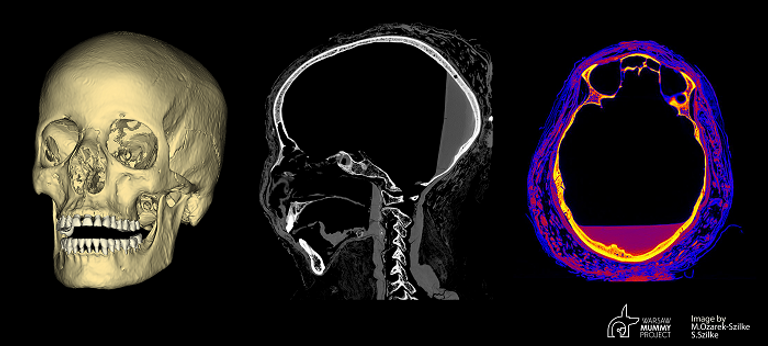

وخلال مقابلة خاصة هي الأولى مع موقع عربي، كشف مديرا المشروع فويتشخ إجسموند، و مارزينا أواريك زيلكي، لـ "العين الإخبارية" عن تفاصيل هذه الاكتشافات، وأعلنا عن بحث جديد يجري حاليا لبناء وجه المومياء الحامل.

وأضافا: "منذ بداية المشروع كنا نركز من بين أمور أخرى، على البحث عن آثار للأمراض القديمة، وخاصة السرطان، وتمت مكافأة سنوات طويلة من الدرسات الدقيقة من خلال اكتشاف التغيرات المرضية في عظام الجمجمة والتي تشير إلى سرطان البلعوم الأنفي، ونعمل حاليا مع البروفيسور رافاي ستيك والبروفيسور توماش ستوكوسا من جامعة وارسو الطبية لإجراء اختبارات الأنسجة الوراثية والجزيئية لمعرفة المزيد ليس فقط عن مومياواتنا ولكن أيضًا عن السرطان نفسه في العصور القديمة.

يشير موقع التغيرات على العظام إلى هذا النوع من السرطان (سرطان البلعوم الأنفي)، لكي نكون متأكدين تمامًا، نحتاج إلى إجراء فحص الأنسجة كما في حالة المرضى الأحياء، وفي حالة مومياواتنا، التشخيص ليس مؤكدا بعد ، ولكن الأكثر ترجيحًا، نريد تأكيده ومعرفة المزيد، في ظروف أخرى، على سبيل المثال، كان من الممكن العثور على جمجمة بهذه الميزات في موقع تنقيب في بولندا، ولكن بدون الأنسجة الرخوة، كان من الممكن تصنيفها على أنها تحتوي على آثار للسرطان.

ما زلنا نحاول الكشف عن هويتها، ونود معرفة اسمها ومزيد من التفاصيل حول حياتها، ونرغب في تحديد تاريخ المومياء بالكربون لتحديد متى كانت تعيش، وأيضا، نحن نعد منشورا لإعادة بناء وجهها، والذي تم إعداده من قبل 2 من المتخصصين الجيدين حقا، فبحثنا مثل تحقيق الشرطة أو رواية غامضة، فهو مليء بالمفاجآت والتحولات.

كان من المهم جدًا بالنسبة لنا أن يتم تأكيد الحمل من قبل أخصائي الحمل وأخصائي أمراض النساء ووصفه بالتفصيل، وقمنا أيضًا بفحص الكثافات الإشعاعية (ما يسمى بوحدات هونسفيلد) للأنسجة وأجزاء مختلفة من الجنين والمنسوجات والأعضاء المحنطة وقارنناها بدراسات الأشعة المقطعية الأخرى المنشورة لمومياوات مصرية وغير مصرية.